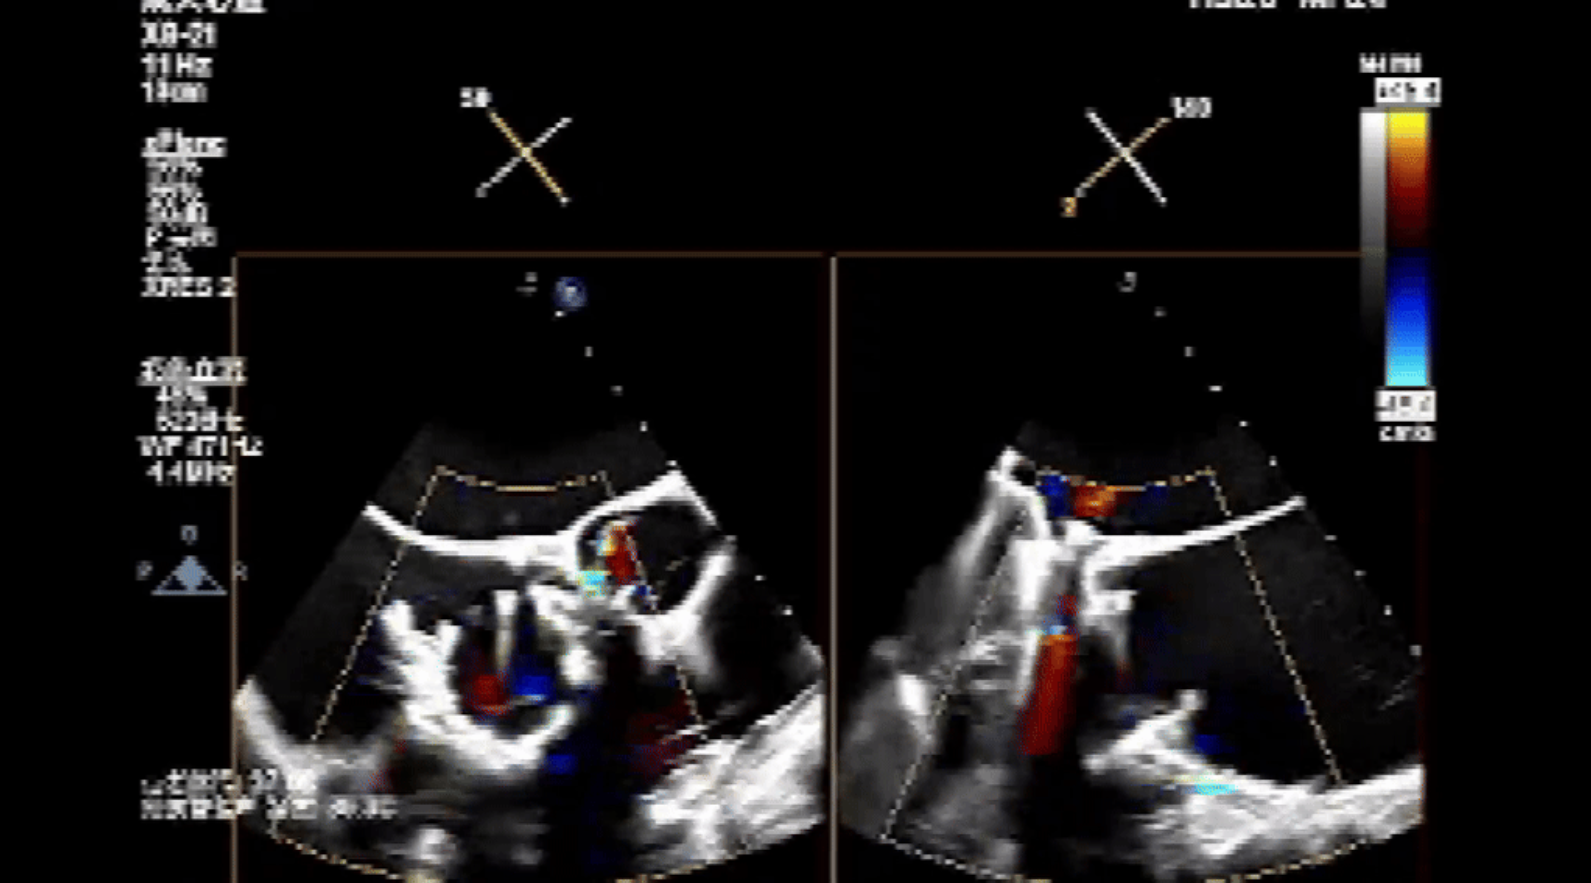

術(shù)前心臟超聲提示:三尖瓣大量返流,右心房容積明顯增大,三尖瓣瓣環(huán)顯著擴(kuò)張。

術(shù)后心臟超聲提示:Lux-Valve Plus植入術(shù)后,三尖瓣瓣環(huán)處可見人工瓣膜回聲,未見返流,人工瓣膜穩(wěn)定,瓣葉開閉良好,連續(xù)多普勒估測(cè)三尖瓣平均跨瓣壓差僅為1mmHg。